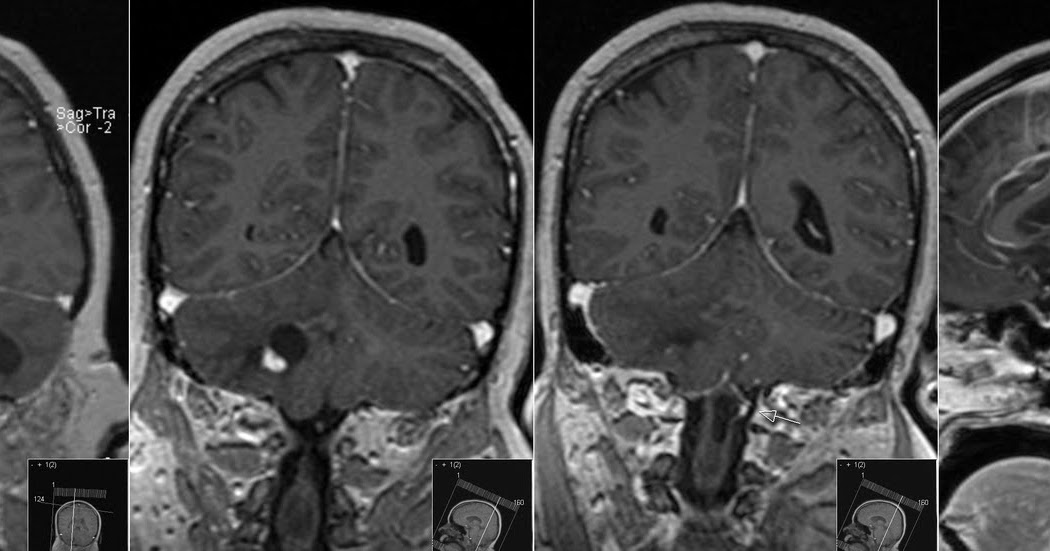

From radiopaedia.org

Hemangioblastoma (multiple) Image Hemangioblastoma Radiosurgery In rare cases where surgery is not feasible, stereotactic radiosurgery, a type of hemangioblastoma radiation therapy, can send. Stereotactic radiosurgery (srs) and radiotherapy (srt) have their roles in the treatment for cns hemangioblastomas, either. Stereotactic radiosurgery (srs) is a noninvasive treatment option that delivers high doses of radiation precisely to the tumor while. Supratentorial hemangioblastomas are often associated with the. Hemangioblastoma Radiosurgery.